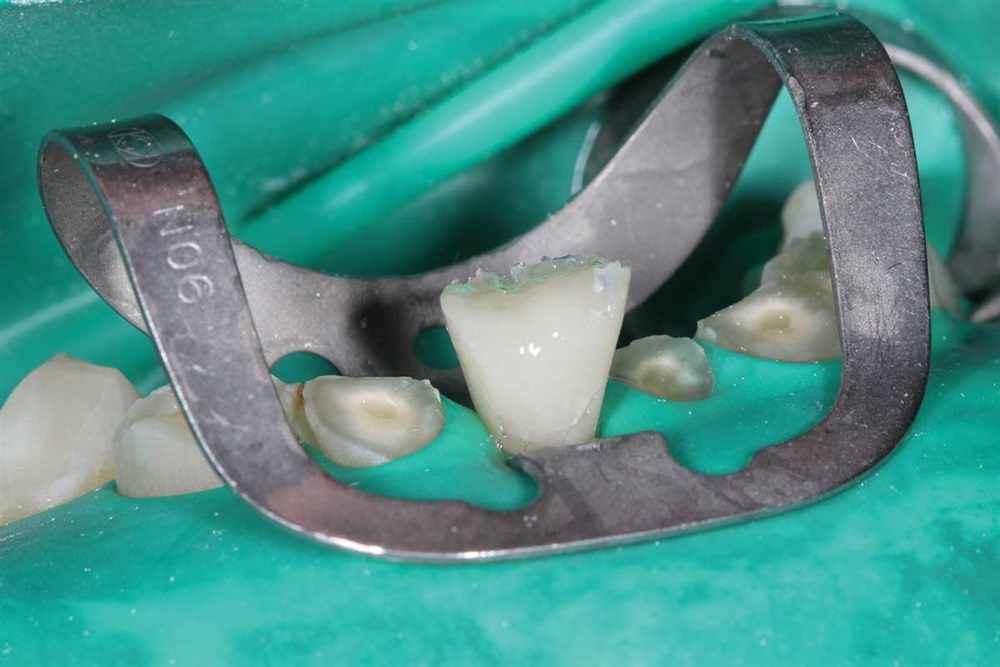

Show Your Work

Fig. 7: Z250 A2 composite, AllBond 2 and Premier Dental Cure-Thru matrix bands were used.

Fig. 8: First tooth done, but not finished. I built up the incisors about 5mm.